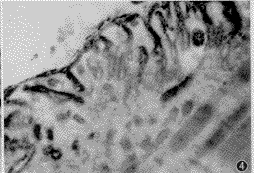

4.术后18及24周:术后18周再生神经纤维全部长入NMJ中, 神经末梢与突触后膜具有良好的接触, 其内突触小泡丰富, 次级突触裂隙及皱襞结构较成熟, 卫星细胞增生不明显。突触后膜N-AchR免疫活性物质继续增多, 平均为健侧的0.83倍(图4), 与术后12周相比, 差异有显著性意义(P<0.05)。 但仍低于健侧, 差异显著(P<0.05)。 术后24周神经末梢结构与术后18周无明显区别,N-AchR免疫活性物质平均为健侧的0.81倍, 与术后18周相比差异无显著性意义(P>0.05)。

图4 神经修复术后18周神经肌肉接头及AchR超微结构。突触小泡丰富, 次级突触裂隙及皱襞结构较成熟, 卫星细胞增生不明显。突触后膜N-AchR免疫活性物质继续增多。电镜×12 000